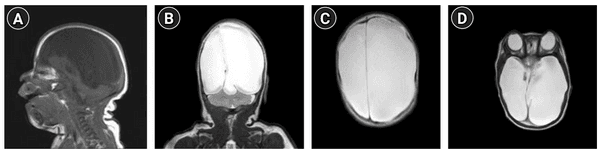

환자의 뇌 MRI사진

[출처] Kim BG, et al. Clinical Manifestations of Hydranencephaly: A Case in Monochorionic-Diamniotic Twin. Ann Child Neurol. 2021 Apr;29(2):105-107。

(그림1. 환자의 뇌 MRI사진. 두 개내 뇌실질이 뇌척수액으로 대체되어 있다.)